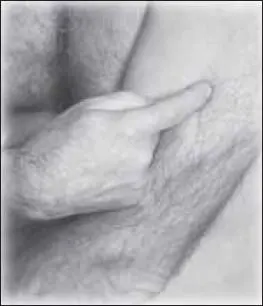

Начинаем с точки би-нао (расположена на месте прикрепления дельтовидной мышцы к плечу) (рис. 109).

Затем воздействуем на точку тянь-фу (расположена на передней поверхности плеча, на месте пересечения дельтовидной и двуглавой мышц) (рис. 110).